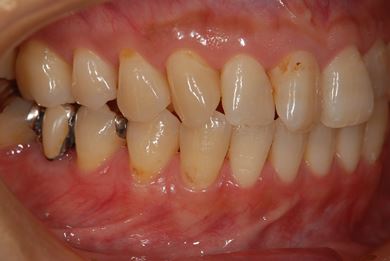

| 性別/年齢 | 女性 / 46歳 | ||||||||||||||||||||||||||||||||

| 主訴 | 左奥歯のインプラント治療を希望。 | ||||||||||||||||||||||||||||||||

| 治療方針 | 左下奥、欠損部分をインプラント治療にて、機能的・審美的回復を行う。 | ||||||||||||||||||||||||||||||||

| 治療内容 | インプラント2本、ハイブリッドセラミッククラウン2本 | ||||||||||||||||||||||||||||||||

| 総治療費 | 399,000円 | ||||||||||||||||||||||||||||||||

| 治療期間 | 5ヶ月 |